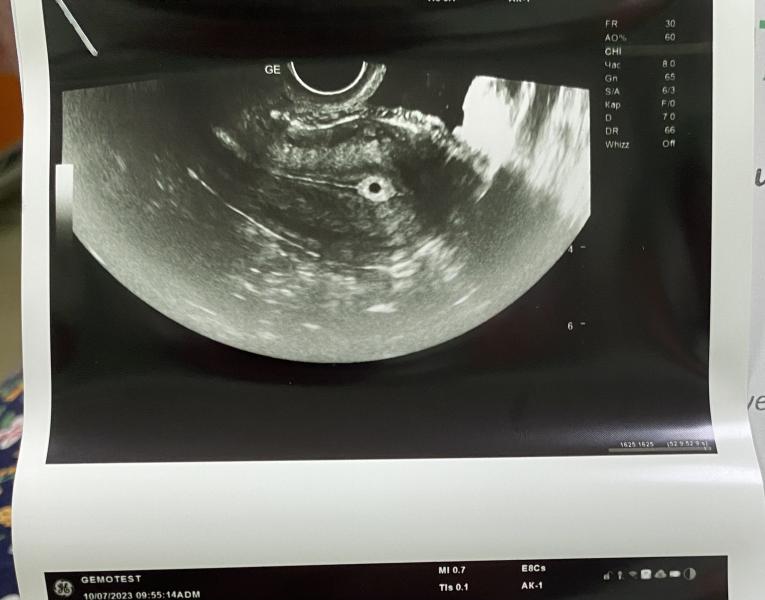

У кого был эндометрий тонкий? Главное чтоб не было выкидыша, так как сказали он должен еще прикрепиться🫣 срок 1-2 недели… хгч сдала тоже завтра будут готовы, сдавать в динамике отслеживать

Мне на 3-4 недели не увидели нечего.